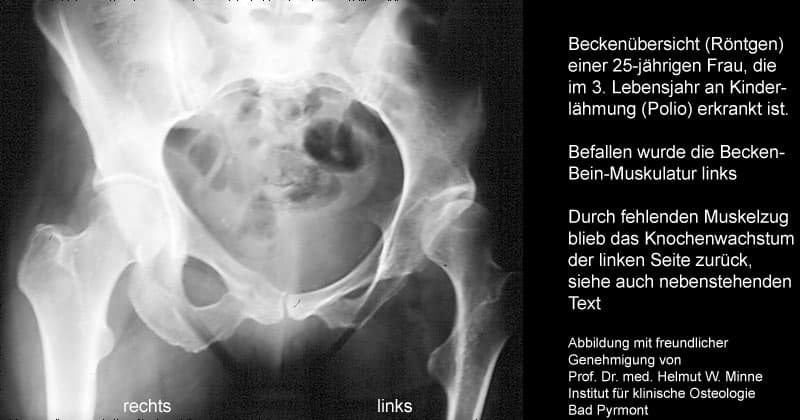

1 Ohne Belastung bleibt das Wachstum der Knochen zurück. Beispiel: Ein 3-jähriges Mädchen erkankt an Kinderlähmung (Poliomyelitis). Befallen ist die Becken-Bein-Muskulatur links. Durch fehlenden Muskelzug wird das Knochenwachstum der linken Beckenhälfte und des linken Beines nicht stimuliert.

Die nebenstehnde Abbildung zeigt das Röntgenbild (Becken und Hüft nahe Oberschenkel) der inzwischen 25-jährigen Frau.

Die Beckenhälfte, Hüftgelenk und Oberschenkel der linken Seite sind "unterentwickelt", kleiner ausgebildet und haben einen geringeren Gehalt an Kalzium. Deswegen erscheinen Sie im Röntgenbild "dunkler".

Die rechte Beckenhälfte, Hüftgelenk und Oberschenkel haben sich durch normalen Muskelzug normal entwickelt.

Bedenken Sie: beide Seiten unterliegen dem gleichen genetischen Einfluss und der gleichen Versorgung mit Hormonen, Kalzium und Vitamin D3.

Das zurückgebliebene Knochenwachstum links ist alleinige Folge des fehlenden Muskelzuges.